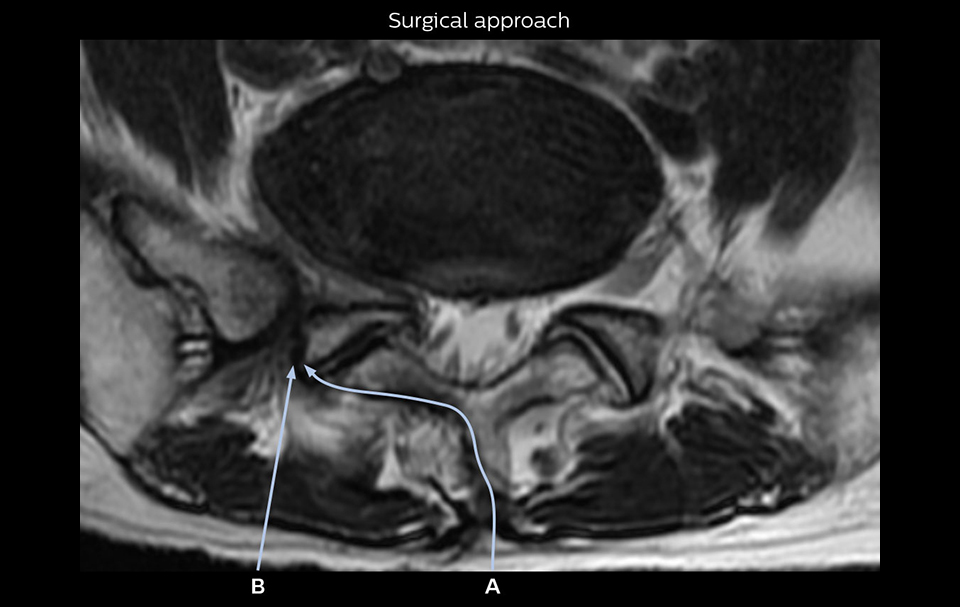

“Recently, the two surgical methods extreme and oblique lateral interbody fusion (XLIF and OLIF) have become mainstream for minimally invasive treatment of lumbar spinal canal stenosis and intervertebral foramen stenosis. With these surgical techniques, the spine is approached from the flank, and prior knowledge of the exact anatomy of the lumbosacral plexus would be extremely helpful. To that end, high slice resolution (less than 1 mm acquisition) that enables sharper sagittal MPR images will be needed.”